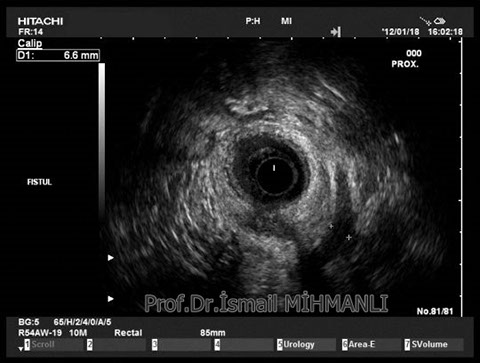

PERİANAL FİSTÜLLER Perianal fistül ve abselerin intersfinkterik anal bez iltihabından kaynaklandığı düşünülmektedir. Crohn hastalarında perianal enflamatuvar hastalık sıktır. İntersfinkterik mesafedeki enfeksiyon yukarıda rektuma, aşağıda cilde, yanlarda dış sfinkteri geçerek iskiyoanal mesafeye uzanabilir. Primer fistülün sfinkterler ile ilişkisini ve abse veya sekonder dal varlığını ameliyat öncesi bilmek, tedavi planı açısından önemlidir. İskiyoanal ve iskiyorektal mesafe tutulmamışsa hastalık daha kolay tedavi edilir. Bu mesafelerde abse veya sekonder bir dal varsa fistül komplekstir ve tedavisi kompleks olmayan fistüle göre değişik olabilir. Bundan dolayı, primer fistül traktı anatomik yerleşimine göre geleneksel olarak sınıflandırılır. Bu sınıflama dörde ayrılır: 1- İntersfinkterik (iç ve dış sfinkter arasında), 2- Transsfinkterik (dış sfinkteri geçerek iskiyoanal veya iskiyorektal mesafeye ulaşmış), 3- Suprasfinkterik (intersfinkterik plandan yukarı doğru uzanan traktüs puborektal kasın Genel Gaz ve Dışkı Kaçırma (Anal İnkontinans) Perianal Fistüller Rektal Tümörler Anal Tümörler Kabızlık Yazılarımız üstündeki bir seviyeden yana kıvrılarak tekrar aşağıya iskiyoanal mesafeye uzanmış), 4- Ekstrasfinkterik (sfinkterlerin dış tarafında rektumdan direkt olarak perianal cilde uzanan traktüs). Endoanal ultrason ile hem primer fistül, hem de varsa sekonder dal ve abse doğru bir şekilde tanınır. Endoanal ultrason ile fistülün anal kanala açılan kısmını (iç uç) görmek kolaydır. Bu hastalarda sfinkter defektlerine de rastlanmaktadır. Sfinkter defekti endoanal ultrason ile kolaylıkla tespit edilir. (bkz. anal inkontinans) Perianal fistül şikayeti olan hastaların az kısmında endoanal ultrason ile bir şey görülemez ise endoanal ultrason probuna ek olarak lineer prob ile anal kanal çevresine bakmak yararlıdır. Çünkü anal kanal bileşenlerinin uzağındaki bir enflamasyon ancak bu problar ile tanınabilir.

İntersfİnkterİk fİstül TRANSSFİNKTERİK FİSTÜL